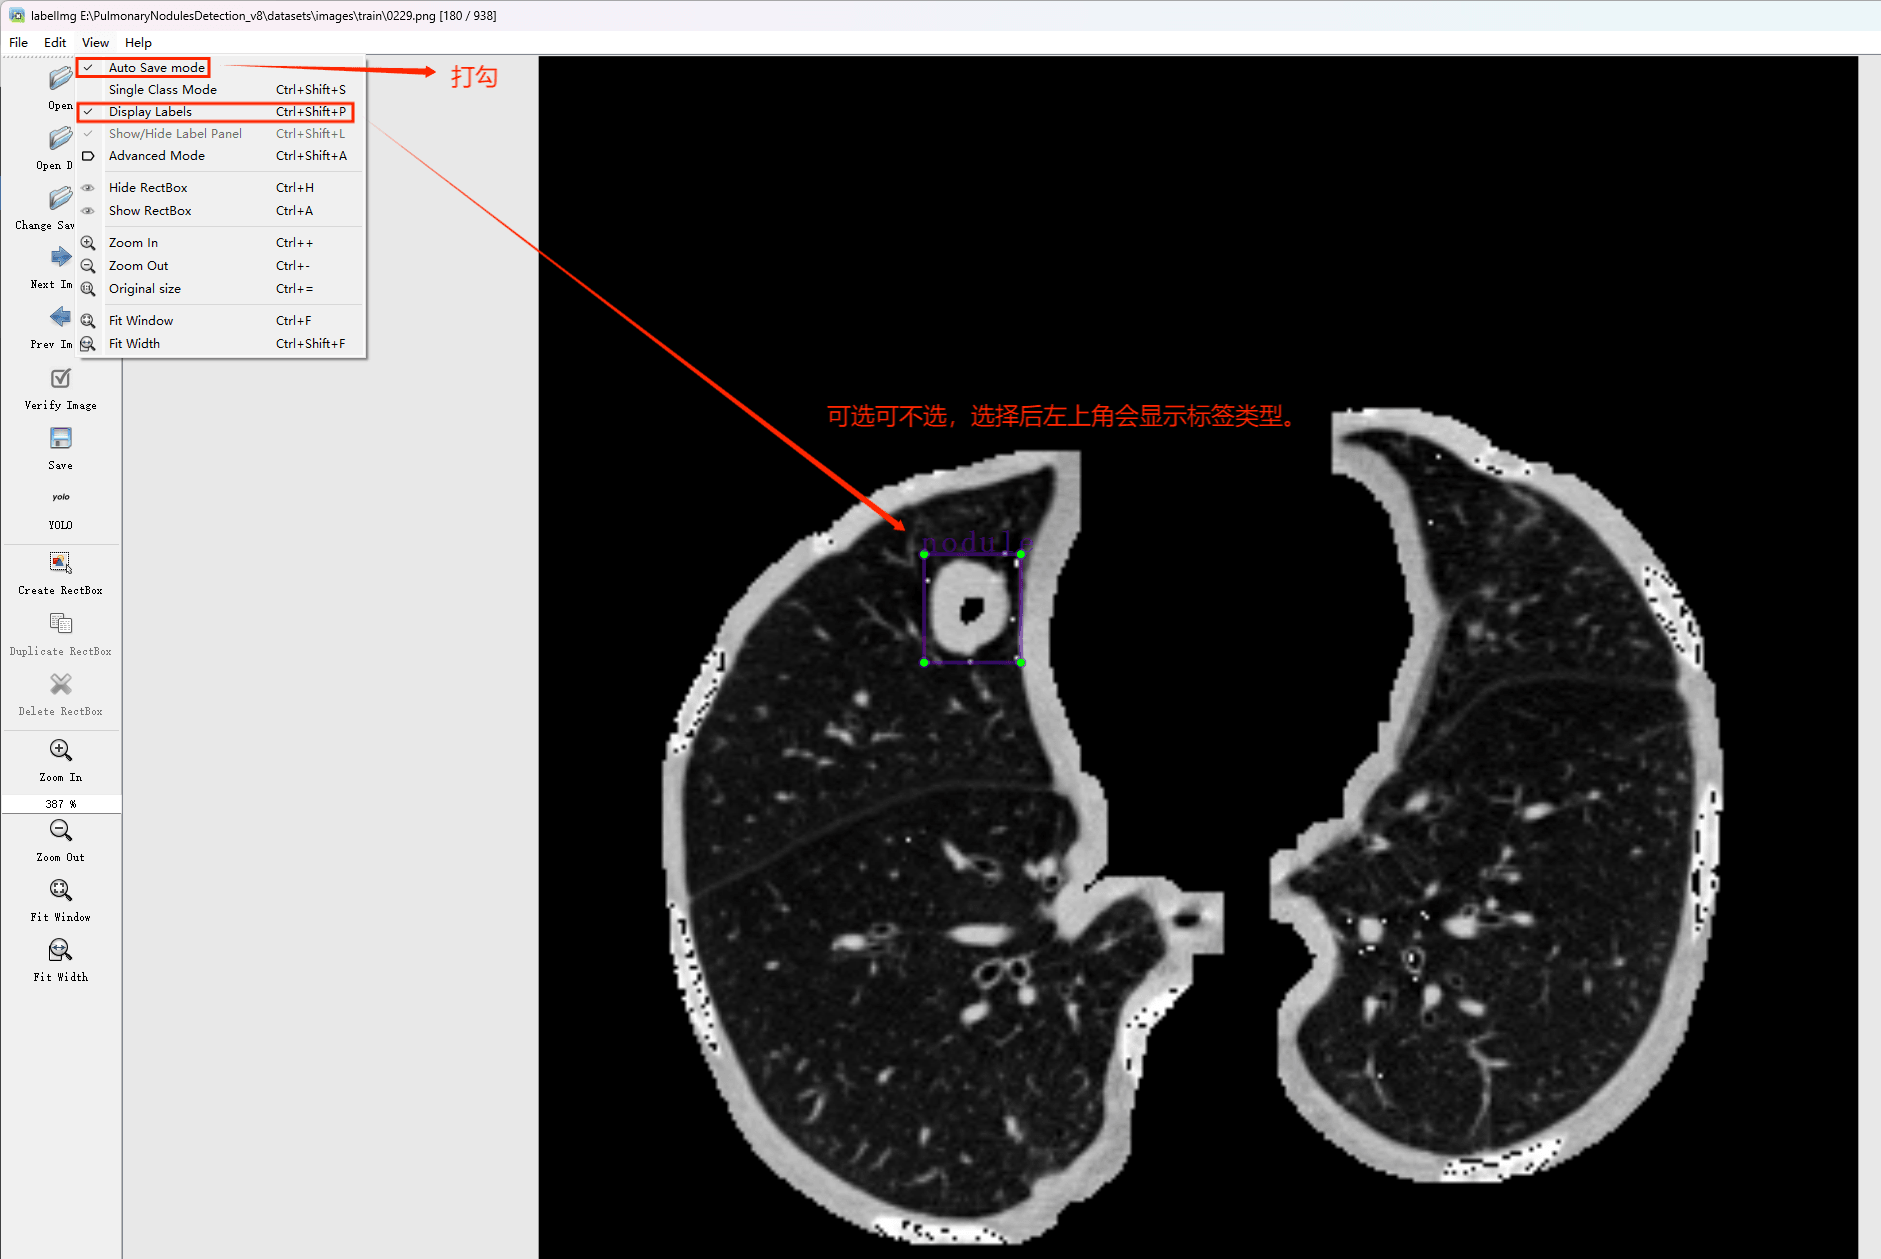

目标检测标注工具

(1)labelimg: 免费提供的一种图像标注工具,默认支持分类标签和目标检测功能,默认采用Python编写,并基于Qt构建了可视化的图形界面,默认操作简单且易于上手(尽管是英文界面)。该软件默认以PASCAL VOC格式保存标注结果为XML文件,默认适用于ImageNet数据集的使用场景,并支持COCO数据集格式的应用场景。(2)在CMD中安装labelimg可通过以下命令完成:pip install labelimg -i https://pypi.t tuna.tsinghua.edu.cn/simple

结束后,在cmd中输入labelimg

初识labelimg

打开后,我们自己设置一下

在View中勾选Auto Save mode

接下来我们打开需要标注的图片文件夹

并配置好存储位置(如上图所示为Change Save Dir)

随后开始操作流程:首先进行标注工作;接着使用框选工具进行选择;然后为选定的目标对象贴上相应的标签;之后按下快捷键D截取下一张图片;如此反复操作直至完成任务。